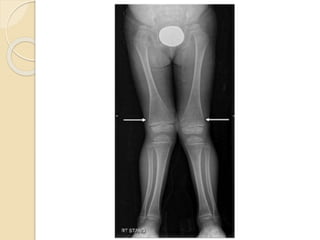

 AP Radiograph of

both lower limbs

obtained 2 years

after active disease

phase shows

bowing of tibia and

fibula and

transverse sclerotic

bands at the

metaphysis parallel

to the growth plate

(Harris growth

arrest lines or park

lines)

 AP Radiographof both lower limbs obtained 2 years after active disease phase shows bowing of tibia and fibula and transverse sclerotic bands at the metaphysis parallel to the growth plate (Harris growth arrest lines or park lines)